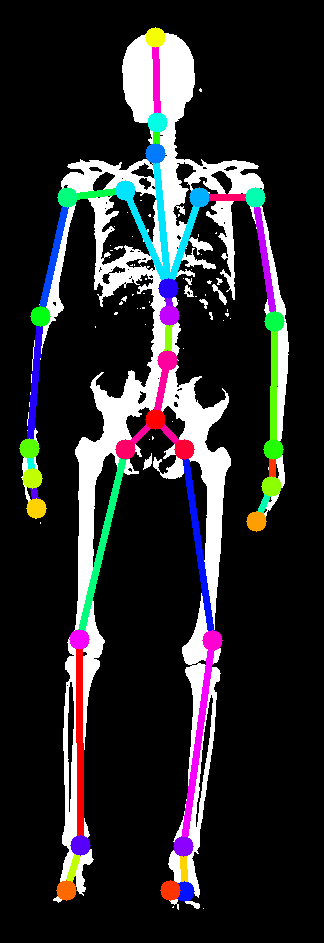

In this work, we address the problem of inferring the human anatomic skeleton, i.e. the bone shapes and locations, solely from surface observations. That is, we infer the bones from the skin. To that end, we learn a statistical model of the skeleton shape and its correlation with the skin surface (Fig. 1 left). Given a posed body, our method predicts the skeleton from the body shape, and poses it inside subject to anatomic constraints (Fig. 1 right).

5.4 Generalization to new poses